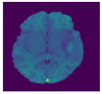

A brain tumor can be defined as a cancerous or noncancerous mass or development of abnormal cells in the brain. Gliomas can be categorized into High-Grade Glioma (HGG) and Low-Grade Glioma (LGG), based on the pathological assessment of the tumor. Brain tumor segmentation seeks to separate healthy tissue from tumorous regions. This is a crucial step in analysis and treatment planning to improve the possibility of effective treatment. Nowadays, biological science has emerged with several extended research problems under the category of Digital Image Processing (DIP). The detection of the tumor and its classification, detection of the cancerous region and its classification, testing, and inspecting crucial parts of the human body are some applications that fall under this category. Out of various medical science problems, automatic brain tumor segmentation and detection is of utmost importance, and efforts are being made in order to effectively handle this problem. A January 2020 Cancer.net editorial approved a report that estimated that this year, 23,890 adults, i.e., 13,590 males and 10,300 females, will be identified with cancerous tumors of the brain and spinal cord in the USA. In general, brain tumor diagnosis usually starts with Magnetic Resonance Imaging (MRI). The suspicious regions are separated using magnetic resonance segmentation using a complicated clinical imaging process. MRI is the most commonly used process that highlights the tumorous region in the brain, although brain tumor detection is still a manual process, examined and validated by experts. Thus, we require a compelling process to identify brain tumors in the early stage to save patients with high accuracy. There are some issues in the manual process, due to which the automatic detection of brain tumors becomes pivotal. Computer-aided detection of abnormal growth of tissue is primarily motivated by the necessity of reducing human error and thus achieving maximum possible accuracy. Using automated algorithms for the accurate and robust predictions of overall survival for patients diagnosed with gliomas can provide valuable guidance for diagnosis and necessary treatment. Furthermore, there is a lack of skilled Oncologists and Neurologists, especially in developing countries. According to a report in 2018, the country is facing a severe shortage of caregivers, with merely 2000 oncologists looking after around 10 million patients (https://timesofindia.indiatimes.com/india/India-has-just-2000-oncologists-for-10-million-patients/articleshow/50842842.cms). Owing to the presence of abnormalities, no conventional technique can be developed for the segmentation of brain tumors in the medical field. Generally, magnetic resonance image (MRI) scans are utilized for the proper examination and diagnosis of brain tumors. This study systematically works on the detection of brain tumors using MRI images []. Owing to the profound significance of machine learning and deep learning, a vast number of methods have been developed, mostly using a specific technique, i.e., machine learning or deep learning []. Despite initiating a breakthrough in handling tumor detection tasks, existing applied deep learning models have some drawbacks. CNN-based deep learning techniques require high volume data, which makes it a complex and expensive task. Massive features are necessary to train tumor detection and segmentation accurately. However, the U-net model of CNN has shown great help in prognosticating in medical image segmentation. In recent literature, numerous works are done either using variation in U-Net architecture or with some pre/post-filtering for outcome improvisation. A Multi-Inception-UNet architecture is proposed to improve scalability and is applied to BraTs 2015, 2017, and 2019 datasets []. This is considered the latest work done in this same direction with the help of this same U-Net Model. MRI Brain Tumor segmentation is validated using 3D-UNet on the BraTs’20 dataset, where the author achieved an accuracy of 0.83 on the training set and 0.82 on the validation set []. The proposed work is somewhat motivated by the work done by Jurdi et al. in June 2020; in their work, U-Net with Bounding Box Prior is applied to two public datasets—SegTHOR is Computed Tomography (CT) images and another Cardiac dataset is a mono-modal MRI dataset. A bounding box (BB) filter is inserted at the BBConV Layer, by which researchers can achieve approximately 98.32% average dice coefficient []. Henceforth, in this study, a systematic process is performed for the detection of brain tumors using MRI images. The experimentation uses U-Net to exhibit the knowledge of deep learning models for tumor image segmentation. The deep learning model is applied for MRI segmentation on the BraTS 2018 dataset (https://www.med.upenn.edu/sbia/brats2018/data.html), which contains four different MRI modalities—T1, T2, T1Gd, and FLAIR of each patient (see Figure 1).

Figure 1.

A sample set of T1, T1-GD, T2, and T2 Flair images (Source: BraTS 2018 Dataset).

Corresponding to each patient, the segmented tumor region and OT (ground truth of tumor segmentation) are stated. Although experiments are primarily carried out on the BraTS dataset, a list of datasets used to perform brain tumor detection tasks is also tabulated in Table 1 for the readers’ point of view.